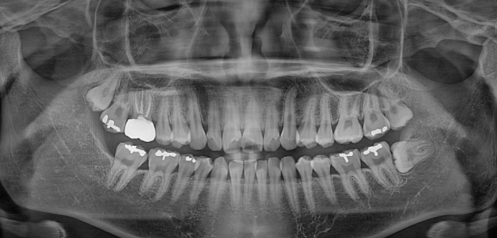

치과에 처음 내원하시면 찍는 일명 큰사진으로 불리는 "파노라마 촬영"이며 10 μSv 입니다.

표준촬영 3장과 파노라마 촬영 1장은 거의 맞먹는 방사선량을 보입니다.